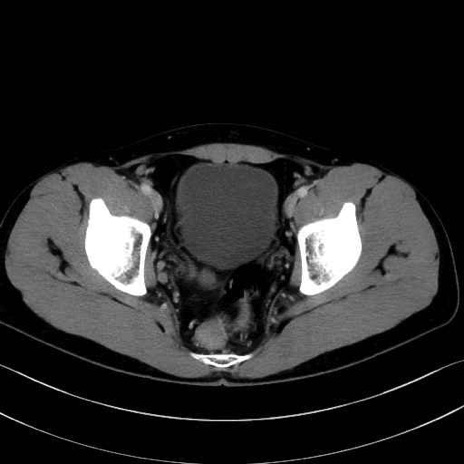

精嚢(seminal vesicle)のCT画像における解剖

症例

【症例】20歳代 男性 スクリーニング